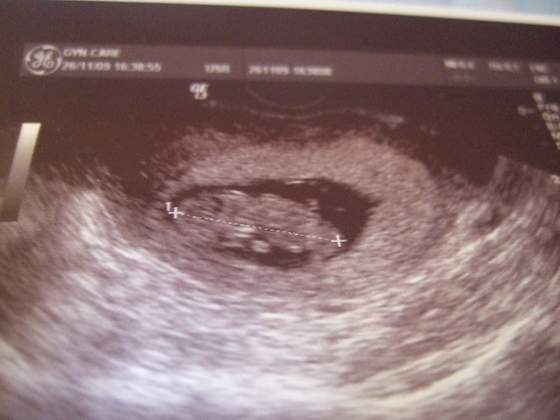

Anik79 -śliczne maleństwo

Dzięki! Udało się! Tak więc widzicie moją fasolkę po raz pierwszy!

babcia fasolki zauważyła, że ona ma oczki i uśmiechniętą buźkę :-)